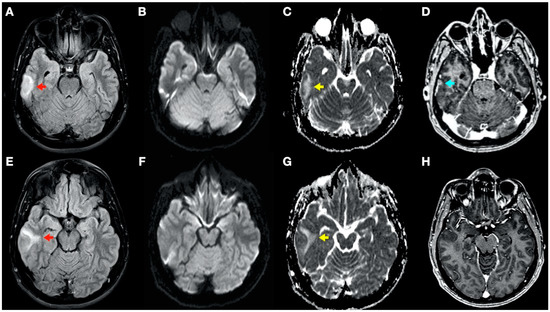

During admission, the following complementary examinations were performed: brain magnetic resonance imaging (MRI; Figure 3, Figure 4 and Figure 5) showed right temporal and left frontal cortico-subcortical lesions, probably secondary to neurological involvement of DCS; neurosonological study of supra-aortic and intracranial arteries showed no atheromatosis or significant hemodynamic alterations; blood tests, including biochemistry, hemogram, coagulation study, serology and autoimmunity, were normal; transthoracic echocardiography was normal (including negative agitated saline contrast study for right-to-left shunt); and total body CT scan showed no evidence of neoplastic process.

Figure 4.

Brain magnetic resonance imaging (MRI): Images (A–C,E–G) from MRI 4 days after clinical onset; images (D,H) from MRI 5 days after clinical onset. Axial fluid-attenuated inversion recovery (FLAIR) images (A,E) show a right temporal cortico-subcortical hyperintense lesion with slight mass effect (red arrows). Axial diffusion-weighted imaging (DWI) sequences (B,F) did not show a high-signal intensity of lesions, whereas axial apparent diffusion coefficient maps (C,G), show a hyperintense lesion in this location (yellow arrows). (D,H) Axial gadolinium-enhanced 3D T1-weighted imaging (Gd T1WI) shows the presence of a slight enhancement of irregular morphology (blue arrow).

In this complex scenario, we report an uncommon case of DCS in a spearfishing breath-hold diver. The diver had a high-risk dive profile, with repetitive breath-hold dives to a maximum depth of about 30 m for several hours and short surface intervals. He had a good response to hyperbaric chamber treatment (US Navy Table 6) and was clinically asymptomatic. Neuroimaging findings showed hyperintensity in long-TR sequences (FLAIR, T2WI), as well as in ADC mapping, and no hyperintensity in DWI sequences, compatible with the presence of vasogenic edema in the left frontal and right temporal lobes (Figure 3 and Figure 4). Regarding MRI perfusion, in the contrast enhancement area, there was an increase in cerebral blood volume (CBV) in relation to the contralateral side and normal subcortical white matter. In the average curves, the area under the curve was higher in the enhancement zone than in the other two zones, which would indicate an increase in perfusion (Figure 5). Initially, given the atypical nature of the lesions, with irregular enhancement in T1WI with intravenous contrast (although their radiological characteristics were not suggestive of neoplastic etiology) [22,23], an extension study with body CT was completed, showing no presence of neoplasia. Likewise, prior to the neuroimaging study, a vascular study (neurosonological, echocardiographic) was performed, as was an extensive blood test study, with no pathological findings. The radiological evolution of the lesions tended towards resolution, with minimal chronic lesions persisting, compatible with small areas of cerebral malacia (Figure 6).

Thus, in our case, the brain lesions found had the typical radiological features of vasogenic edema. This allows us to exclude, in this case, the ischemic nature of the process (e.g., secondary to arterial occlusion), which would show radiological characteristics of acute ischemic injury (cytotoxic edema) in one or more cerebral vascular territories, as well as a reduction in CBV in MRI perfusion maps. The findings of the radiological evolution contributed to this. Follow-up MRI demonstrated complete resolution of the FLAIR/T2WI signal abnormalities, confirming reversible vasogenic edema, since cytotoxic edema formation and infarction lead to gliotic lesions in the brain and consequently result in permanent signal alterations (hypersignal in long-TR sequences) [24]. Diffusion-weighted MRI reflects the Brownian motion of water molecules within the tissue, thus providing data on tissue integrity. DWI and ADC mapping have mainly been used for the detection of acute ischemia (cytotoxic edema) and for distinguishing between cytotoxic and vasogenic edema [25]. In addition, the ADC map is an MRI image that shows diffusion more accurately than conventional DWI by removing the T2 weighting that is inherent in conventional DWI.